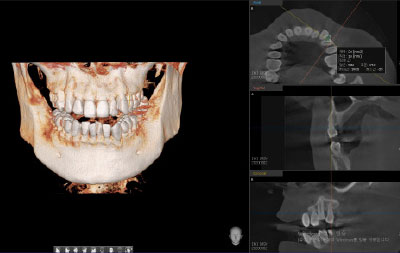

拍摄CT & X光片

Computed Tomography / Panorama

[ 拍摄CBCT ]

牙科CBCT拍摄是利用X线

3D视频重现牙槽骨和牙齿的硬组织 .

[ PANORAMA ]

确认整个牙齿的现状和

排列, 咬合, 颚关节状态 .

可确认牙槽骨吸收, 牙根炎症,

修复体的状态, 牙齿的状态等等 .